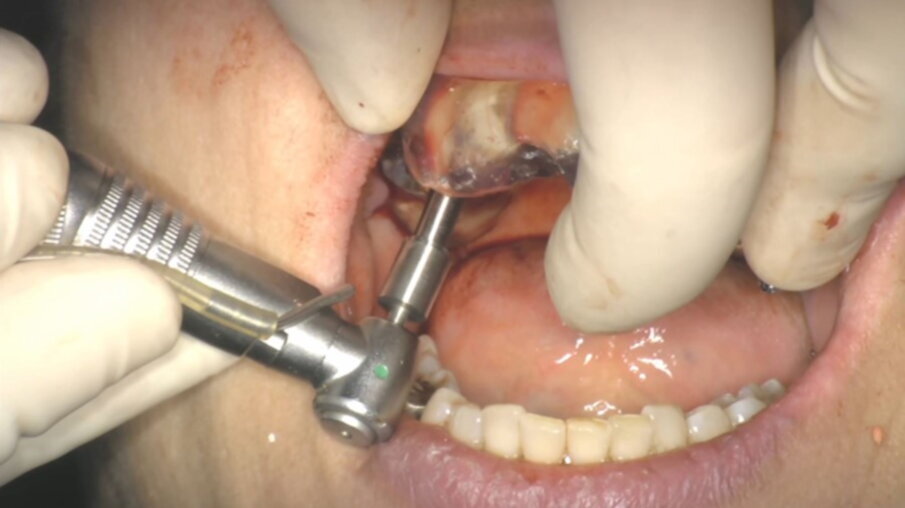

Figg. 1, 2_Situazione iniziale.

Fig. 3_Dopo l’estrazione dei denti 1.6, 1.7, 2.6.